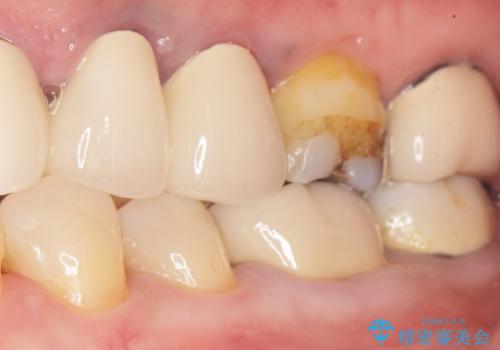

精査したところ、左下の奥歯(左下5)のプラスチックの詰め物と歯の境目が虫歯になり、黒くなっていました。

古い詰め物とう蝕を除去し、審美的で適合が良く二次う蝕になりにくいセラミックインレーによる修復を行いました。

審美的な仕上がりと自然な咬み心地に喜んで下さいました。

インレーの種類:セラミックインレー(e-max press)